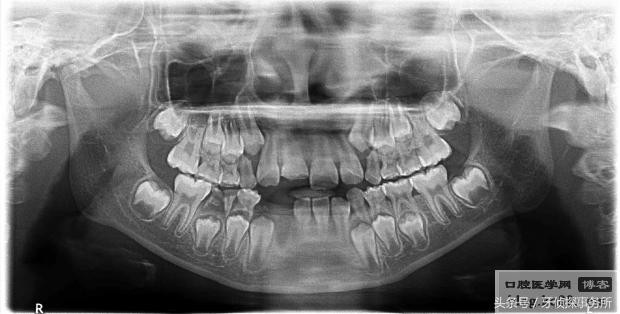

1、部分脱位

碰撞后乳牙在外力的作用下向外或向内倾斜移位后部分脱出牙槽窝时,可将外伤牙恢复到原位后结扎固定,一般预后较好,但日后有可能发生牙髓坏死,根尖感染或牙槽脓肿。如果接近替牙期或者乳牙牙根已吸收1/2以上者可以考虑拔除该颗松动乳牙。

3、嵌入性脱位

嵌入,即牙齿陷入牙槽骨。如果伤及恒牙牙胚需要将嵌入的乳牙复位;如果是在替换牙期,可以将嵌入的乳牙拔除;其他情况可以不必处理,等乳牙自行长出。